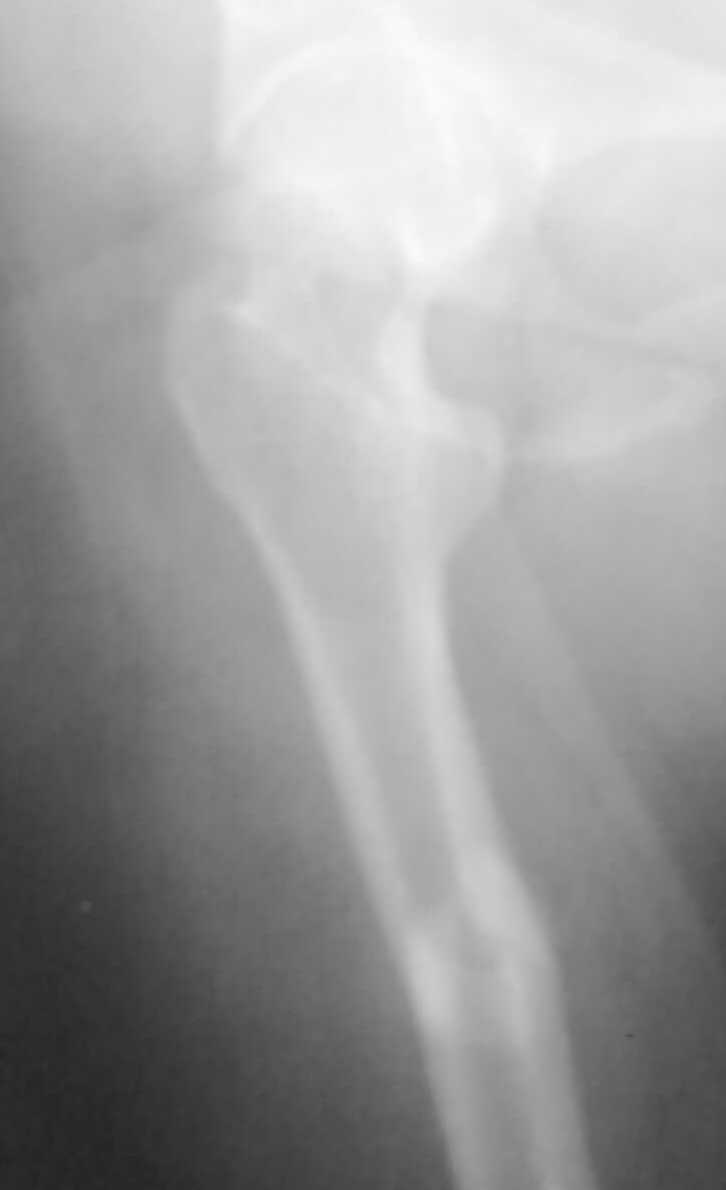

Немного добавьте подробностей pls - что за перелом? На снимке его толком не видно. Какие имплантаты доступны?

Перелом поперечный с незначительным смещением и с захождением отломков около 2,0см. Перелом типа А 1.

Если доступны гвозди с блокированием, какие еще рассматривать варианты для диафизарного перелома бедра, и почему?